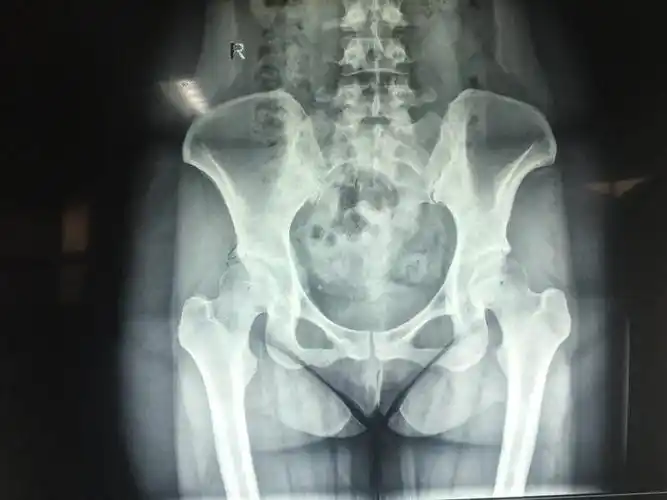

髋关节疼痛,x光及mri检查

髋关节正位片

右侧股骨头形态完整,内密度不均匀,可以多发斑片状低密度影,髋关节